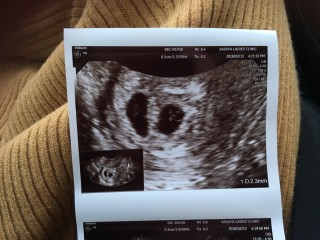

3回の人工授精と2回の体外受精を経て妊娠しました。前回は、化学流産で胎嚢確認できなかったので、胎嚢と卵黄嚢が見れて嬉しいです。大きさは13.3mmでした。

このまま、順調に成長してくれることを願って2週間後の心拍確認に臨みます!!